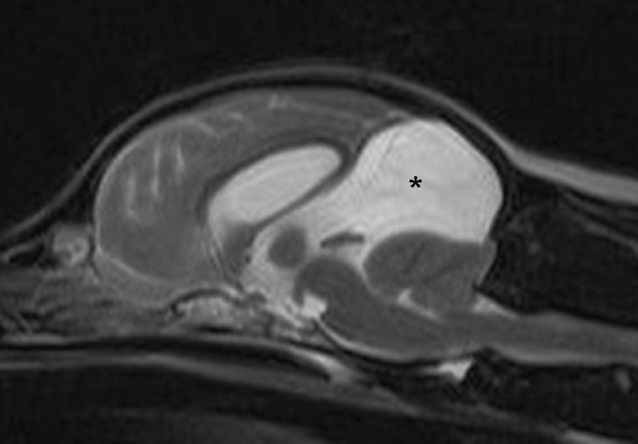

MRI ακολουθία Τ2 σκύλου με ενδοκρανιακό αραχνοειδές εκκόλπωμα *

Η οριστική διάγνωση απαιτεί προηγμένες απεικονιστικές μεθόδους. Η μαγνητική τομογραφία (MRI) αποτελεί τη μέθοδο εκλογής, καθώς παρέχει λεπτομερείς πληροφορίες για το μέγεθος, την εντόπιση και την επίδραση του εκκολπώματος στις γειτονικές δομές. Η αξονική τομογραφία (CT) μπορεί επίσης να χρησιμοποιηθεί, αλλά προσφέρει μικρότερη αντίθεση των μαλακών ιστών.